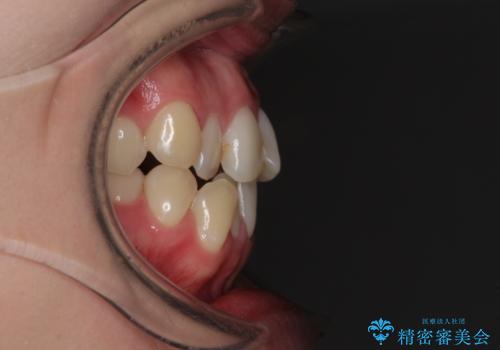

前歯のクロスバイトを治したい インビザラインによる矯正治療

- 前歯のデコボコとクロスバイトを治したいとのことで来院された患者様です。

上下顎ともに歯列全体の側方拡大とIPR(歯と歯の間を削る)によってデコボコとクロスバイトが解消するように設計し、インビザラインにより治療を行うこととしました。

下顎骨の左側への骨格的なずれが強く、上下の正中の位置合わせや奥歯の咬み合わせ構築に苦労しました。